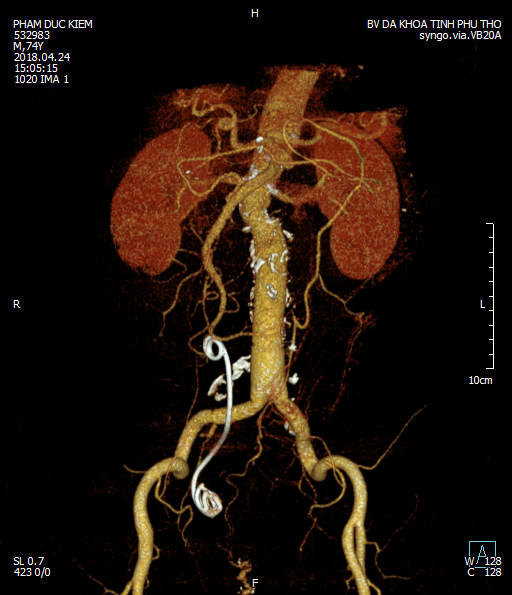

Ảnh dựng chụp bằng cắt lớp 128 dãy

Theo Bác sỹ Hòa, khối máu tụ quá lớn, biến đổi giải phẫu nhiều, việc tìm được động mạch chủ đoạn dưới động mạch thận là vô cùng khó khăn, nguy hiểm, khối phình và máu tụ rất lớn (khoảng 8 cm đập theo nhịp ngay dưới tay), vừa nhanh chóng tìm và kẹp được động mạch chủ, vừa không làm rách khối phình gây chảy máu dữ dội, vừa tránh kẹp trên động mạch thận gây suy thận. Bác sỹ cũng cho biết, tìm được trên động mạch thận cũng rất khó, cao, vướng nhiều thành phần quan trọng: tụy, mạch thân tạng, tá tràng… Sau 15 phút đã kẹp được động mạch chủ và có những lúc vừa phải ấn giữ vào tạm thời hạn chế chảy máu vừa phẫu tích.